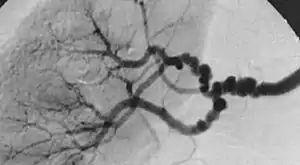

| The "string-of-beads" feature in multi-focal fibromuscular dysplasia. The sign is caused by areas of relative stenoses alternating with small aneurysms. | |

Multi-focal (previously known as medial) fibroplasia involves thickening of the media and collagen formation. It is typically reported as having the appearance of a "string of beads" on angiographic review.[4] "The 'bead' component is often larger than the normal arterial lumen, and in a subset of patients with FMD, aneurysms are present that may require treatment."[4] The multi-focal subtype of FMD accounts for nearly 80% to 90% of all FMD cases.[4]